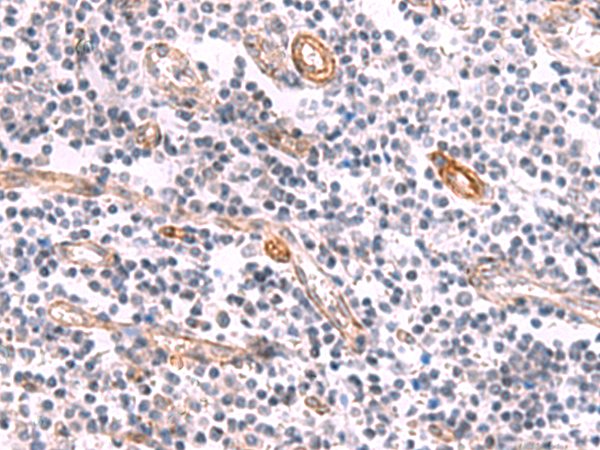

分类: 科研抗体货号: P06776别名: syd; JIP3; SYD2; JIP-3; JSAP1应用: IHC反应种属: Human